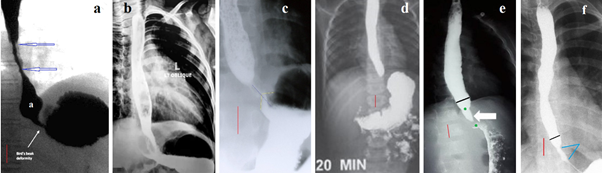

Figure 3 Radiographs of patients with acquired stenosis.

(a) An example of the EGJ image in GERD. The contracted LES is visible as a thin line between the esophagus and the stomach. The presence of a contrast agent suggests mucosal inflammation of the LES. Conical end of the esophagus authors (b,c,e) call the bird's beak sign and on this basis diagnosed EA. (b) A sharply dilated esophagus and a very short distance between the esophagus and the stomach. Arrows indicate a contrast spot in the shortened LES. This is a trap of the contrast agent in the inflamed LES, which indicates deformation of the lumen. (c) The accumulation of a contrast agent in the shortened LES indicates fibrous deformation. (d) The same patient after per oral endoscopic myotomy (POEM). The uneven contours of the gaping LES indicate fibrous deformation of the walls. In another patient, after POEM (Figure 3 g), the contours of the LES are smooth.43 (e-f). Figure (e) shows the level of fluid in the upper part of the esophagus above the long esophageal narrowing (yellow arrow). The second level of fluid in the dilated esophagus is located above the closed LES with a contrast agent trap. Given the long stenosis in the esophagus, there is a high probability that it and the stenosis in the LES are caused by exposure to hydrochloric acid. The child suffered open Heller myotomy and Dor fundoplication.28

In each of the 4 cases there was esophageal dilation over a narrow and very short LES. Small volumes of contrast were trapped in the LES (red arrows). The significant shortening of the LES and signs of inflammation in the esophagus suggest acquired stenosis at the level of the LES, probably due to GERD. No radiographic evidence of EA was found. Bougienage of the LES during intensive treatment of GERD would be more justified than dissection of the LES.

Figure 4

(a-b) A 9-month-old female infant intermittent vomiting, dysphagia and refusal of solid foods began after weaning. She was treated for gastroesophageal reflux. At first, radiological investigation suggested achalasia, while esophagoscopy revealed firm stenosis, which did not allow the passage of the endoscope. She underwent four endoscopic balloon dilatations that then allowed her to swallow solid food with intermittent mild dysphagia. After 17 months of esomeprazole treatment off therapy impedance-pH monitoring was normal.44 (c) After the last dilatation, EGJ patency is normal, but LES function is not visible. Since pH monitoring only detects severe forms of GERD, this child cannot be considered healthy.

(d-e) In a 1-year-old girl vomiting and progressive dysphagia began at the age of 6 months when solid food feeding was started. Esophagography revealed an abrupt narrow segment at the lower esophagus with marked proximal dilatation. The esophagoscopy findings included nonyielding lower esophageal stenosis without evidence of esophagitis. The endoscope (outer diameter, 5.8 mm) could not pass through the stenotic orifice. Resection of a narrow area with end-to-end anastomosis was performed. The diagnosis of congenital stenosis was histologically confirmed.45

(f-g). Preoperative, and postoperative barium esophagogram of a mid-esophageal congenital esophageal stenosis after successful correction.46